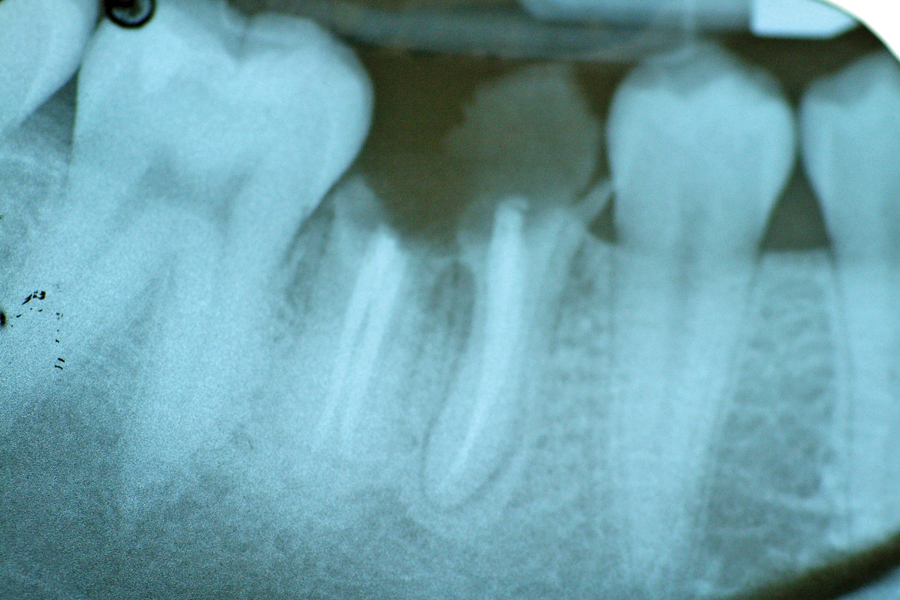

During the last two years, I have placed 65 UFG dental implants in a variety of locations in the mouth. I used these new implants to restore single to multiple missing teeth with traditional fixed prosthesis. During this two year period, UFG titanium dental implants and CP titanium dental implants were compared according to their unique clinical performance. I have been using traditional CP titanium dental implants for approximately 20 years and during this time, I have learned a lot about their familiar clinical performance characteristics. From my personal experiences with CP titanium dental implants, I was well prepared to sort out clinical differences between these two types of dental implants. These new UFG dental implants have been manufactured and prepared to the same exact dimensions and designs of CP titanium dental implants that I have been using for the last 20 years. Both UFG and CP titanium dental implants were manufactured by BASIC Dental Implant Systems, Inc., Albuquerque, New Mexico. Based on my clinical experience, dental implants are ready to restore when they meet the following criteria; 1) Lack of infection around the implant 2) The ability of bone to resist clockwise torque force of the implant to 40 Ncm. 3) Intimate bone to implant body surface contact as seen through traditional Periapical Radiographic examination. Depending on the patient and type of bone, an implant can be ready to restore using CP titanium within two to four months. This protocol has been a standard practice in my clinic for many years. Research has shown that a greater number of bone cells tend to colonize UFG titanium surfaces when compared to CP titanium surfaces. Because of these earlier findings, I wanted to know whether it is possible to restore UFG dental implants earlier, compared to the traditional CP dental implants I have been using for many years. An evaluation period of one to two months was chosen to assess UFG titanium implants for restoration loading instead of the typical period of two to four months for classical CP titanium implants.6 All of the patients treated with UFG titanium dental implants returned at 1 to 1.5 months from the time of surgical placement. At recall, it was quite evident that these UFG titanium dental implants are able to meet restoration criteria significantly earlier when compared to traditional CP titanium dental implants. Periapical radiographs of these novel implants generally show a greater degree of bone maturity at the implant surface when comparing to CP dental implants. Radiographic examinations of UFG dental implants typically show greater bone density at the implant body surface, which generally means more bone on the implant’s surface. The increase in bone cell colonization on UFG dental implants was expected because of the earlier research findings and my findings confirm this earlier research. UFG titanium dental implants have proven that they can indeed be loaded earlier compared to CP titanium dental implants. In my experience, torquing CP titanium dental implants to 40 Ncm, at 1 to 1.5 month periods usually results in movement of some implants, requiring additional time for adequate healing, necessary to meet criteria for restoration. Without exception, all 65 UFG dental implants were more resistant to torque forces at recall appointments much earlier compared to CP titanium dental implants. Breakage of dental implants has never been an issue to worry about when utilizing CP dental implants; therefore I have found no difference here. I have encountered very few broken dental implants in my practice during the past 20 years and I cannot report on the clinical benefits to me of UFG titanium dental implants as result of its increased strength properties. My experience utilizing so-called minimal diameter dental implants is only beginning and as such, the strength of these dental implants will most likely play an important role as I increase the use of these implants clinically. My preference is to avoid implanting dental titanium, which incorporates Aluminum and Vanadium to add strength at the expense of biological issues. A nice benefit of UFG titanium is that it significantly surpasses the strength properties of both CP and Alloyed titanium without Aluminum and Vanadium.7 To date, all UFG dental implants are in function and are recalled at six to 12 month intervals. UFG titanium dental implants have also been provided to other dentists in the USA, Taiwan, China and Russia. These clinicians report clinical observations similar to those described in this paper.